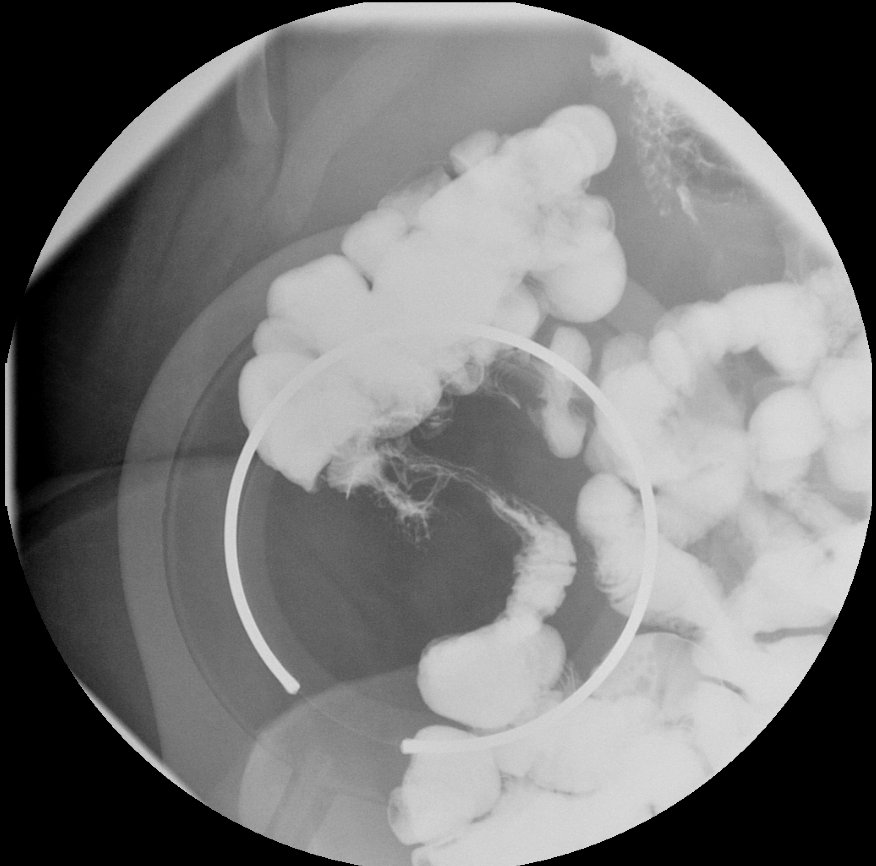

03/10/2022

A 35-year-old woman with a medical history significant only for appendectomy presented to the emergency department with right lower-quadrant abdominal pain over the past 2 weeks.